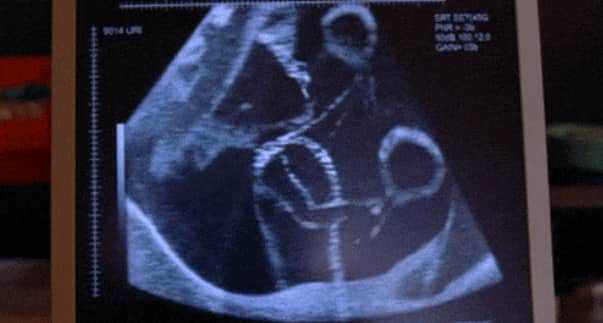

因为随着女性年龄的增长,卵子逐渐老化,带有正常基因卵细胞的百分比逐渐减少。因此随着年龄的增长,女性的生育率会下降,流产率增加,唐氏综合征等出生缺陷的概率增加。35岁以上女性每月怀孕几率开始下降,约为10%左右,一年的累积受孕几率大概为75%。在经过6个月的积极尝试没有怀孕的话,就应该谘询生殖专家了。